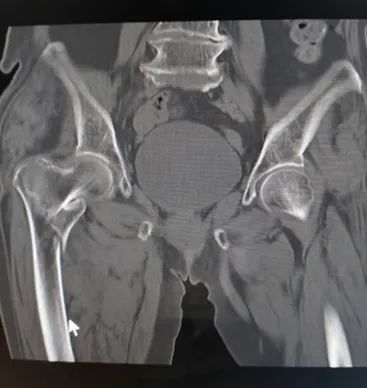

骨折CT表现

2.邻近关节积液、脱位,脊椎骨折可伴有椎体滑脱;